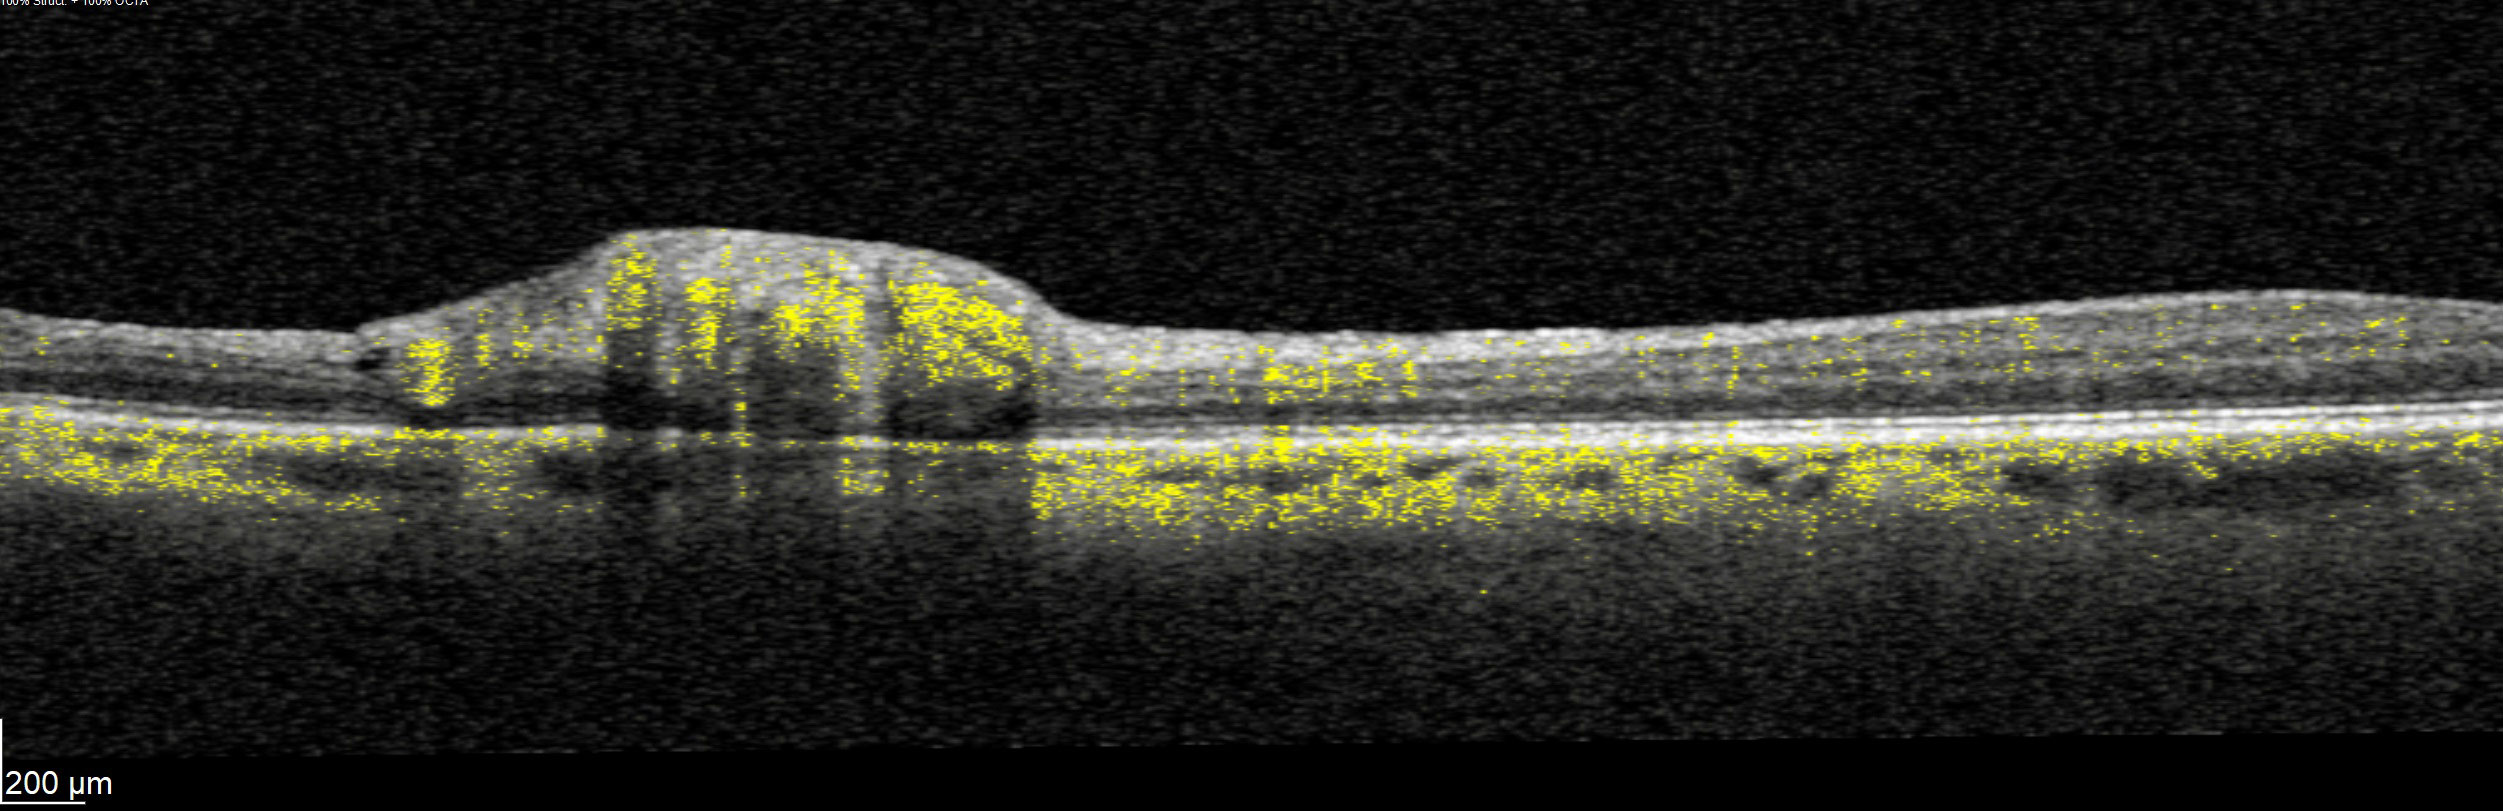

Offering the ideal speed-quality ratio for OCTA, 125 kHz allows you to increase your throughput without any clinically relevant loss in image quality in comparison to the current 85 kHz scan speed. The fast acquisition of images allows for visualization of flow, even in miniscule vessels, while minimizing artefacts, resulting in sharp and detailed images of the capillary network. Additionally, you can decrease chair time when you speed up acquisition with the Glaucoma Module Premium Edition in your glaucoma workflow, if applicable.

SPECTRALIS with SHIFT technology and 125 kHz scan speed empowers you to offer customized diagnostic OCTA imaging of both the retina and the optic nerve head to meet the needs of each individual patient – or adjust to 85 kHz if your patient’s condition requires longer light exposure.

125 kHz – A fast scan speed for improved workflow and high OCTA image quality.